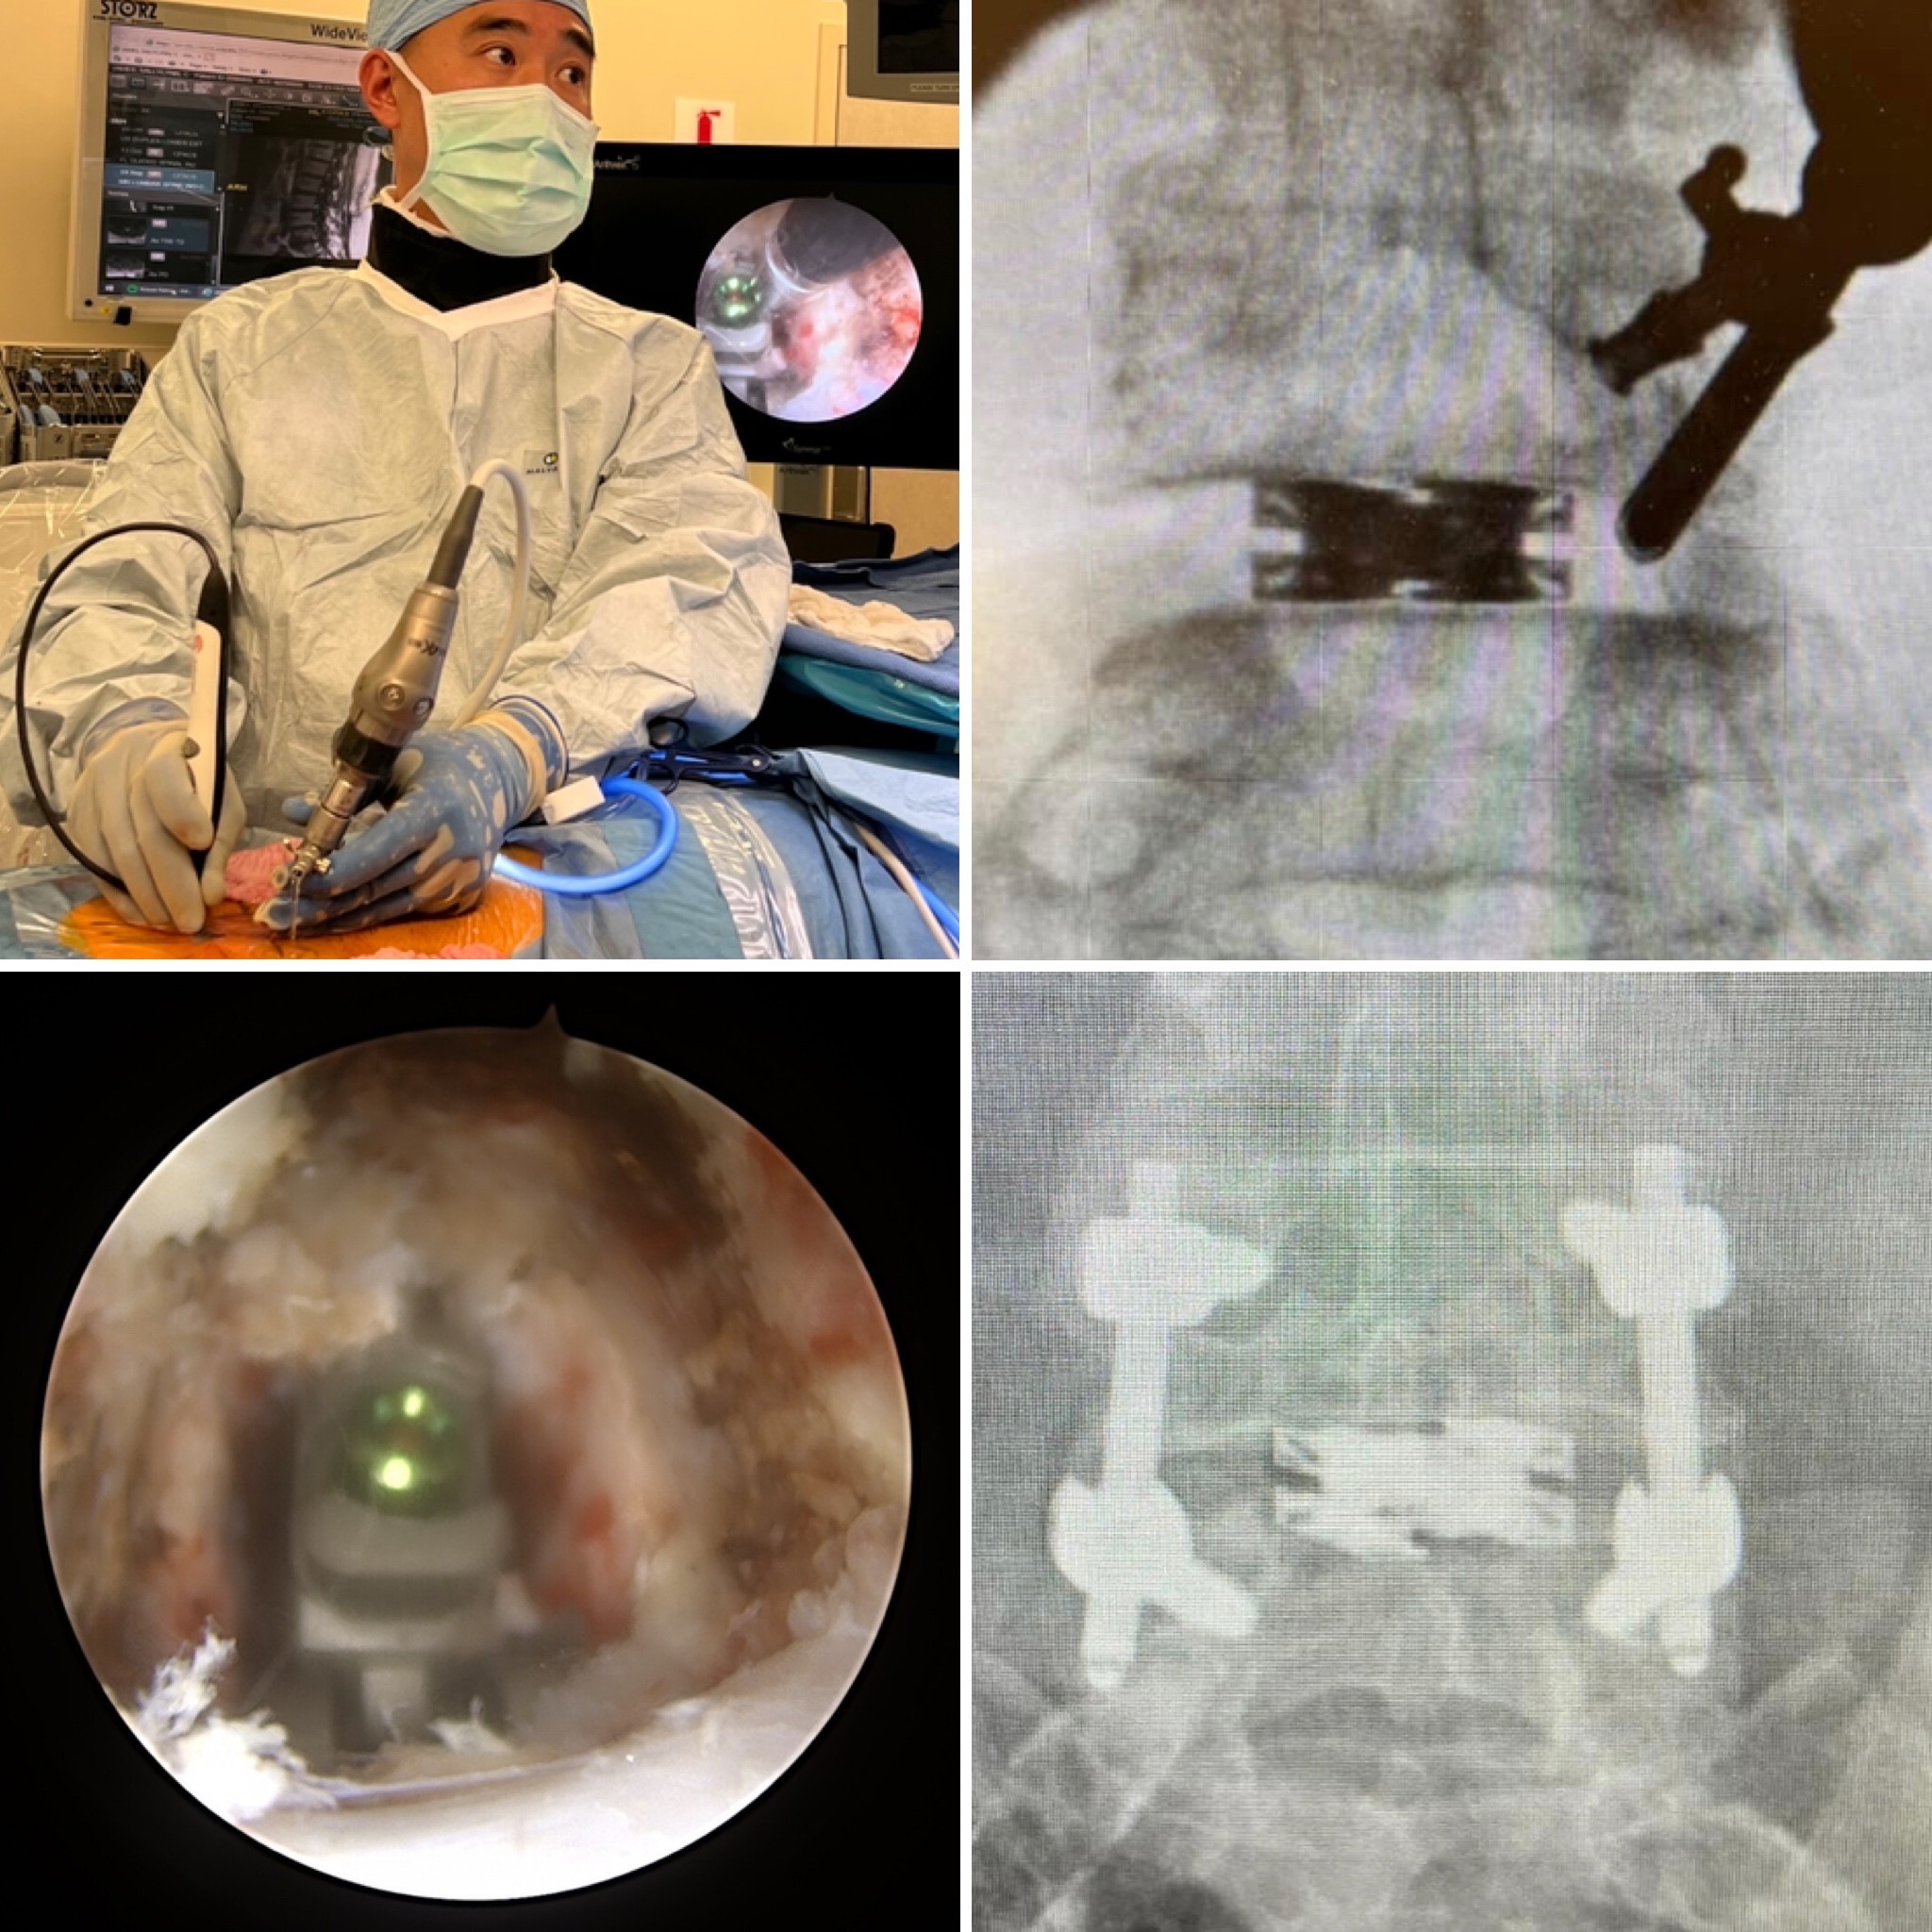

Amplify Surgical will present the latest evolutions in endoscopic spine and minimally invasive lumbar surgery and showcase the expansion of their portfolio with the dualPortal approach, a novel two-portal endoscopic technique, along with dualX, the Dual Expanding Interbody Fusion System.

Dr. Don Young Park, an orthopedic spine surgeon at UCLA Health specializing in minimally invasive spine surgery and one of the very first to perform dualPortal endoscopic surgery in the country commented, “The dualPortal spinal endoscopy is a game-changer that has completely change my practice. It is a truly enabling technique that can be used in any case that was previously performed with microscopes and tubular retractors. The dualPortal approach reduces the learning curve experience with other endoscopic techniques because the visualization of the anatomy is so familiar.”

Dr. Park will be presenting on The Marriage of dualPortal Spinal Endoscopy with dualX TLIF: the dualLIF procedure, an Advancement of Endoscopic Spine Surgery and discussing his experience with dualPortal and dualX with KASS attendees at a workshop on Friday, March 11, at 10:50 am, where attendees will have the opportunity to weigh in on the impact of dualX and the dualPortal endoscopic approach in spine surgery.

The dualPortal technique is a novel two-portal endoscopic approach to the spine that allows surgeons to easily learn and perform a wider array of lumbar spine procedures than the conventional one-portal technique. It also provides flexibility to perform endoscopic lumbar fusions with conventional expandable cages or dualX.

The dualX technology is comprised of a family of titanium expandable interbody devices designed to expand in both width and height, implanted in lateral lumbar interbody fusion (LLIF), posterior lumbar interbody fusion (PLIF) and transforaminal lumbar interbody fusion (TLIF) spinal procedures. The dualX portfolio contains varying footprints, heights and degrees of lordosis with post-expansion bone grafting to provide a customized anatomical fit for a clinically successful fusion environment.